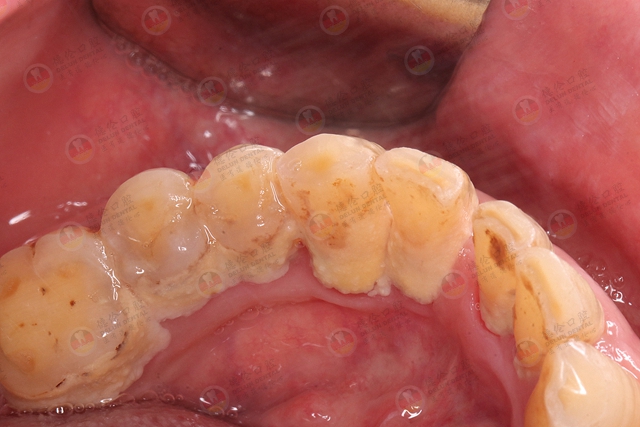

牙周炎始于牙龈炎症,称为牙龈炎。牙龈炎的典型表现是:刷牙的时候,牙龈有出血现象。如果你仔细观察牙齿,还可能会看到牙齿上有颜色异常的物质,这就是牙菌斑。牙菌斑是牙齿上细菌和食物残渣的堆积物,若它没有及时被清除干净,会在牙齿上形成坚硬的牙结石,而牙结石它是牙龈炎和牙周炎的主要的致病因素。